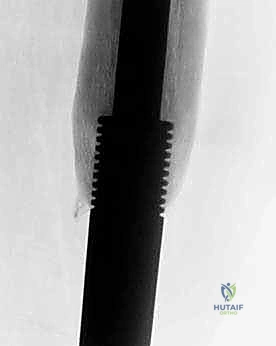

الطرف الاصطناعي القابل للتمدد (Expandable Endoprosthesis) هو معجزة هندسية طبية. يتكون من سبائك معدنية فائقة القوة والتوافق الحيوي (مثل التيتانيوم والكوبالت كروم). يتم زراعته داخل الجسم ليحل محل العظم المفقود والمفصل (مثل مفصل الركبة الصناعي).

- الأجيال القديمة (التمدد الجراحي التدخلي): كانت الأطراف الاصطناعية القديمة تتطلب إجراء عملية جراحية صغيرة في كل مرة يحتاج فيها الطفل إلى زيادة طول الطرف. كان الجراح يقوم بعمل شق صغير، وإدخال أداة لتدوير برغي دقيق داخل الطرف الاصطناعي لزيادة طوله. هذا كان يعني جراحات متكررة، وتخديراً متكرراً، وزيادة خطر العدوى.